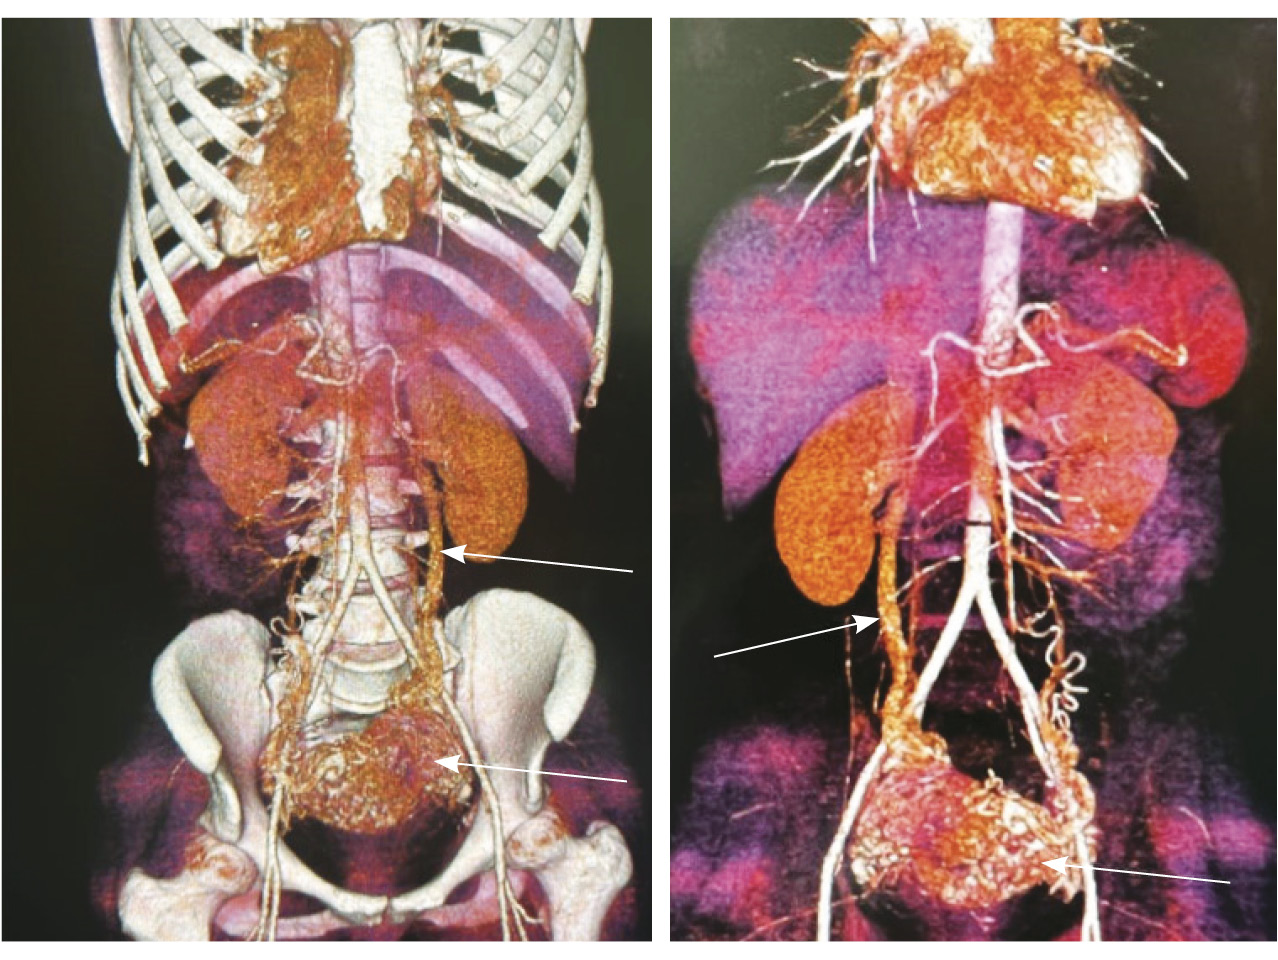

Для детализации сосудистого компонента артериовенозной мальформации, в том числе с целью планирования дальнейшей лечебной тактики, пациентке выполнено КТ-исследование (рис. 3). Обнаружено: тело матки увеличено, определяется образование в полости матки неясного генеза. В стенках матки сосудистая артериальная сеть с ранним сбросом контрастного вещества во внутреннюю подвздошную вену с двух сторон (диаметром 0,7 см справа, 0,8 см – слева), правую яичниковую вену (диаметром до 1,2 см), левую яичниковую вену (диаметром до 0,6 см).

Рис. 3. Компьютерная томограмма органов таза с контрастированием. Тело матки увеличено, в стенках матки сосудистая артериальная сеть (стрелки) с ранним сбросом контрастного вещества во внутреннюю подвздошную вену с двух сторон, правую и левую яичниковые вены (стрелка)